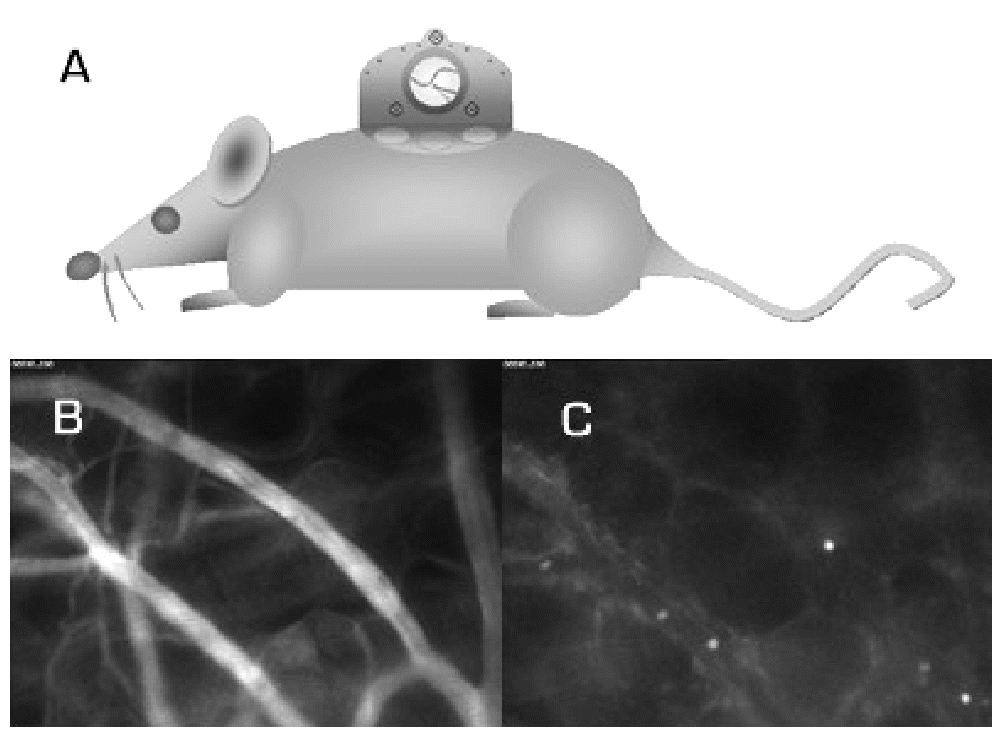

Dorsal skin-fold chamber (A), Measurement of VD (B) and LEI (C) in vivo

Morbidity and mortality in diabetic patients are determined by the vascular complications of the disease. Despite the impact of microcirculatory dysfunction in diabetic disease, little is known about these parameters during the development of diabetes mellitus type 2. Methods: We used UCP1/DTA mice at the age of 12 and 20 weeks respectively, expressing diphtheria toxin A-chain regulated by the promoter of the uncoupling-protein 1. The result is a brown fat deficiency with subsequent development of a metabolic syndrome and a diabetes mellitus type 2. A dorsal skin-fold chamber was implanted (A) and microcirculatory parameters were monitored quantitatively in vivo over nine days using a fluorescence microscope. Fluorescence tracers were injected intravenously to measure vascular density (VD) (B), Leukocyte-Endothelium-Interactions (LEI) (C) and microvascular permeability (P). Furthermore we injected insuline, glucose and triglycerides to control mice and measured microcirculatory parameters thereafter. Results: 20 weeks old UCP1/DTA mice showed a decrease in VD due to a remarkable reduction of small vessels. P and LEI were significantly increased. The altered parameters were correlated to the metabolic dysfunction represented by blood glucose levels. These functional and morphological alterations were also found in 12 weeks old mice, characterized by impaired glucose tolerance. However in 12 weeks old mice with a metabolic syndrome, alterations of microcirculatory parameters were not as much pronounced as in 20 weeks old mice. The stimulation tests with insuline, glucose and triglycerides in control mice showed no acute effects of insuline and triglycerides on microcirculatory parameters, whereas glucose led to an increase in P. Conclusion: From our data we concluded that the development of microvascular dysfunction is a dynamic process at least partially correlated to the elevated blood glucose levels. Mivrovascular alterations at the stage of impaired glucose tolerance underline the necessity of early diagnosis and treatment of the metabolic syndrome and of impaired glucose tolerance to prevent development of microvascular dysfunction. The diabetic model enables us to monitor time-dependent microvascular alterations during the development of diabetes mellitus and evaluate established as well as new anti-diabetic therapies using intravital fluorescence microscopy.